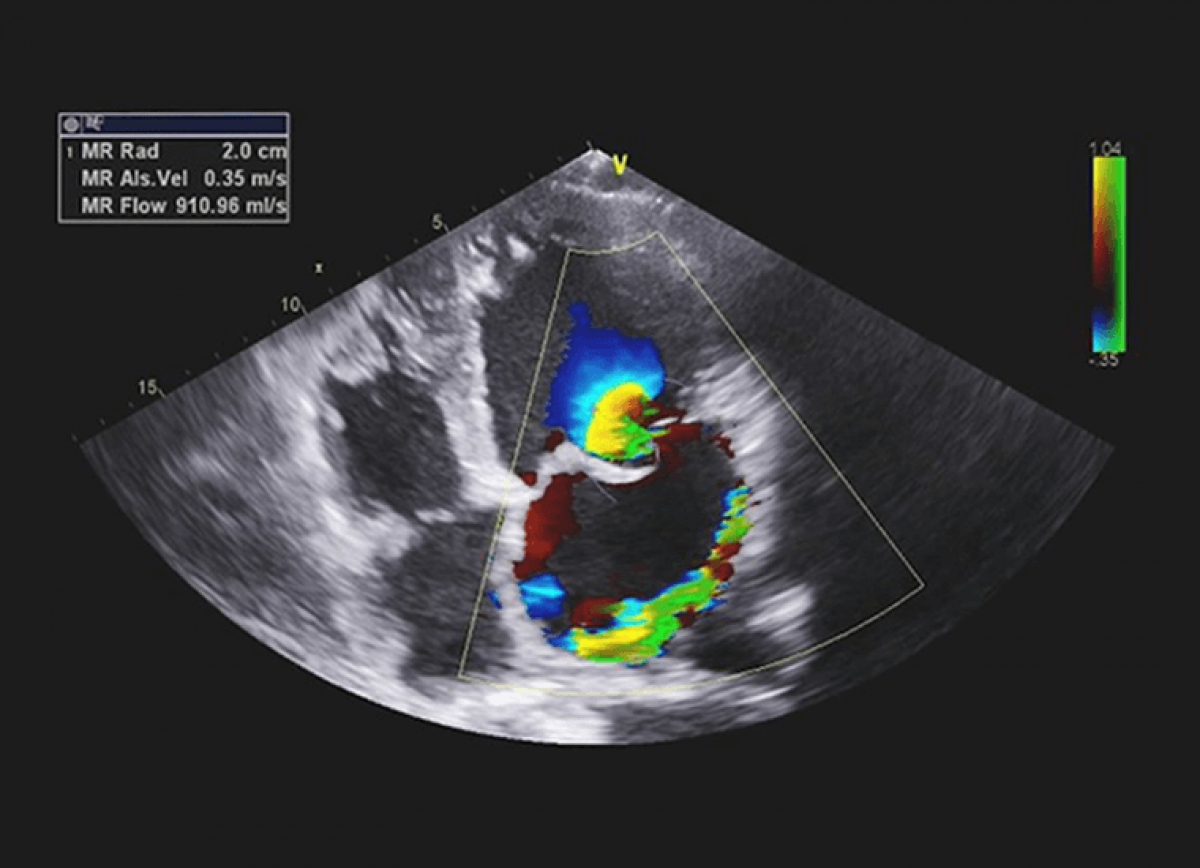

Dwie pacjentki z zaburzeniami rytmu i podejrzeniem wady mitralnej.

Ciężka niedomykalność mitralna na tle wypadania płatka zastawki mitralnej.

Umiarkowana niedomykalność mitralna na tle wypadania płatków zastawki mitralnej (zespół Barlowa).

Echokardiografia przezklatkowa

Ocena niedomykalności mitralnej.